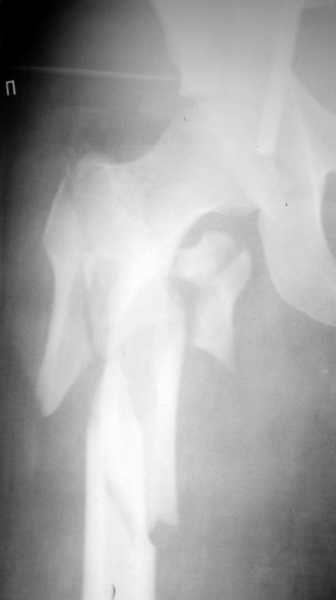

Отправлено Alexander Chelnokov 15 Октябрь 2003, 14:24

К нам переведена пациентка 17 лет с множественной травмой - перелом таза и проксимального отдела бедра (таз уже вправлен и стабилизирован аппаратом "таз-бедро"), плюс еще и многооскольчатый перелом пятки на той же стороне, что и бедро. Вопрос про перелом бедра - чем его лучше фиксировать? Клинковая пластина, DHS, DCS, проксимальный/реконструкционный гвоздь? Больше импонирует последний, но у нас их нет. Возможно, кто-то из производителей/распространителей может предложить приобрести имплантат и дать инструменты напрокат? На каких условиях? Родственники готовы оплатить.Заранее спасибо.

Спасибо, все практически так и получилось - на счастье в наших краях на днях была конференция по ожогам, на которую представители "Деоста" ехали на выставку. Попутно захватили нам реконструкционный гвоздик ChM с набором инструментов.

Оперировали вчера. Не сказать, что все прошло гладко - вертельная область была расколота и в сагиттальной, и во фронтальной плоскости, гвоздь попал в перелом и сместился кзади, что заметили уже после введения винтов, пришлось все извлечь и переставить. Снимки в приложении. Буду признателен за комментарии.